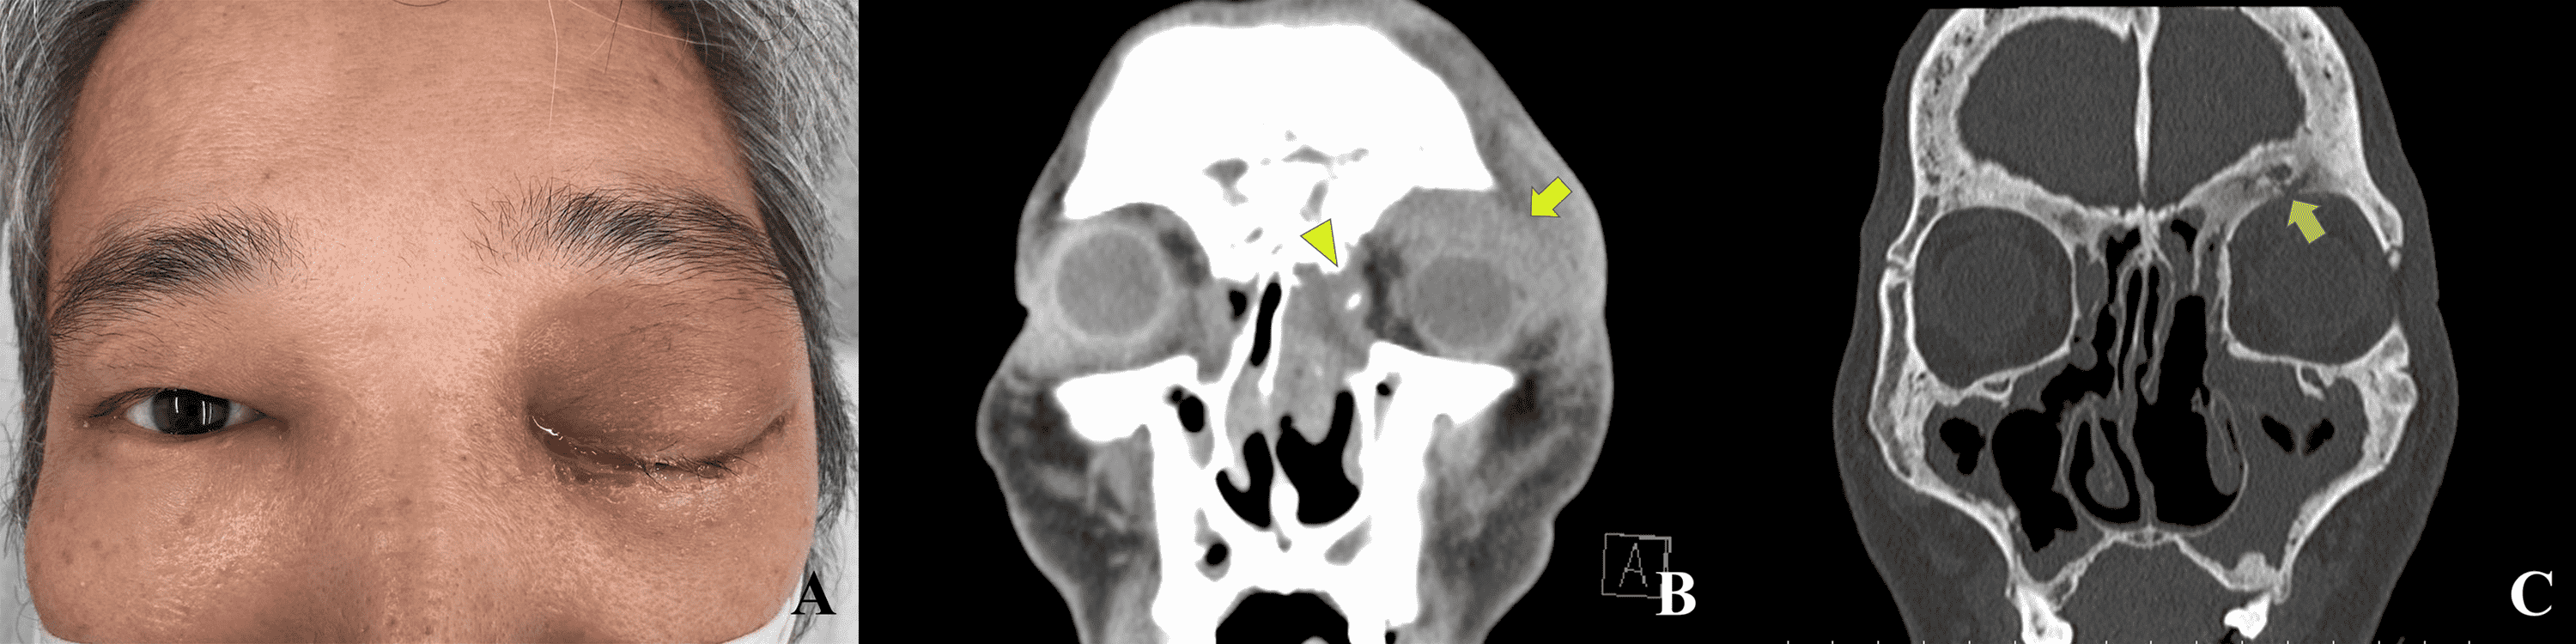

Sonographic Diagnosis of a Retro‐orbital Abscess Secko 2012